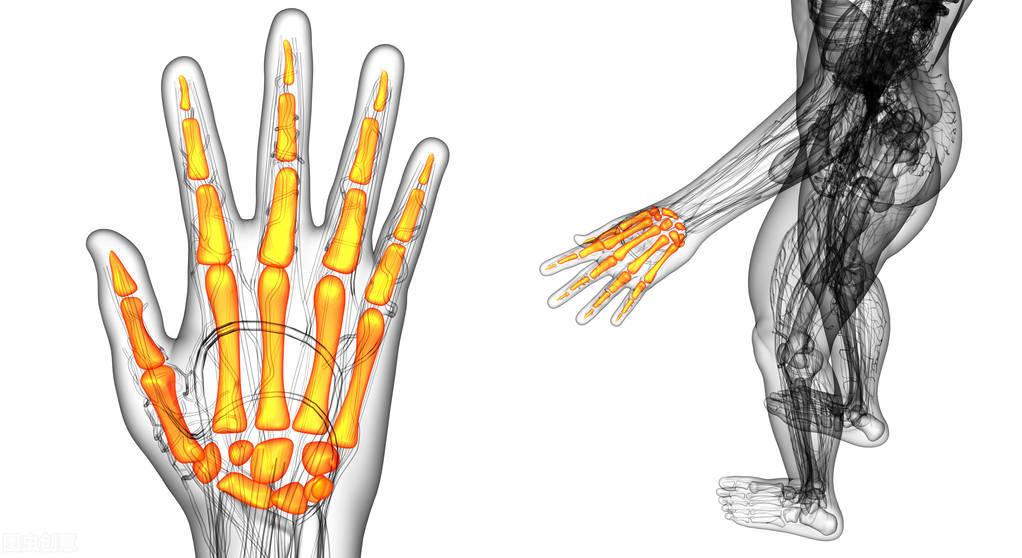

当患者在发生类风湿这种疾病的时候,一定要注意平时的饮食,首先不能吃海产品,因为海产品里面有很多的寒性,也就是我们常说的发物,当病人在吃完海产品之后,就会出现了发烧出疹子症状,很容易引起类风湿这种疾病的。

当患者在出现类风湿这种疾病的时候,不能吃一些辛辣刺激性的食物,如果说长时间吃辛辣的食物的话。这样就会导致消化道不良反应,从而就会引起上火发病,油腻的食物也是刺激性的食物,对患者的消化系统有很大的影响,而且还会导致患者的营养不良。